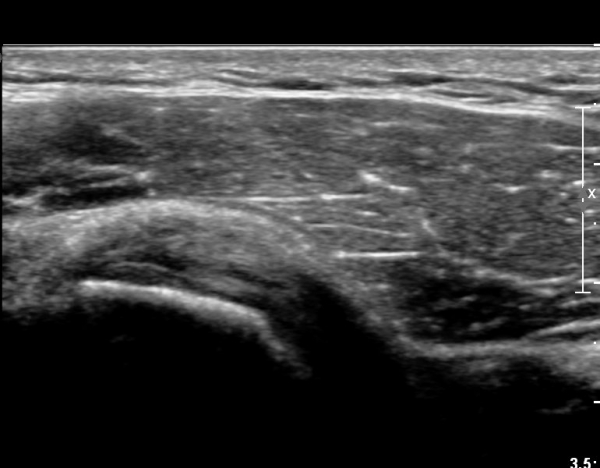

ÃÊÀ½ÆÄ ¼Ò°ß :  ȸÀü±Ù°³ °í¶û  °Ë»ç¸¦ À§ÇÑ »ó¿Ï Á߸³À§¿¡¼­ °ß°©ÇÏ±Ù°Ç °Ë»ç¸¦ À§ÇØ  ŽÃËÀÚ¸¦

¾à°£ ³»ÃøÀ¸·Î ±â¿ï¿© ½ÃÇàÇÑ °ß°©ÇÏ±Ù°Ç Á¾´Ü¸é°Ë»ç¿¡¼­ °ß°©ÇÏ±Ù°Ç »óºÎ°ÇÀÇ

Á¾¹æÇ⠺и®(½ÇÁú³» ÆÄ¿­)°¡ °üÂûµÈ´Ù(»çÁø 1).